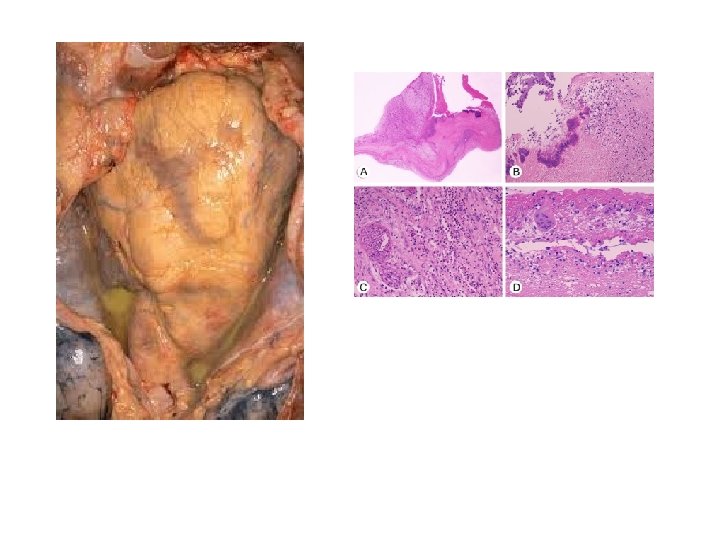

Pathology • Acute serous or serofibrous pericarditis (usually viral) mild inflammatory reaction associated with focal damage to the adjacent myocardium – The response varies: small amount of serous fluid with mononuclear cells and fibrinogen to large neutrophil rich, bloody effusions – Mild fibrosis and adhesion between visceral and parietal surfaces – Constrictive pericarditis (rare) – Usually self limiting and rarely fatal • Acute purulent pericarditis (usually bacterial) – The purulent material contains large number of neutrophil in a large volume of effusion – Healing is associated with extensive fibrosis that may progress to chronic constrictive pericarditis – The mortality rate is 50%

Pathology • M. tuberculosis • 5% of cases with pulmonary TB will have pericardial involvement • Early granulomatous stage: large pericardial effusions (>300 ml), serosanguinous, mononuclear cells • As the disease evolves the inflammatory process become chronic– fusion of parietal and visceral pericardium– consecutive pericarditis and circulatory failure